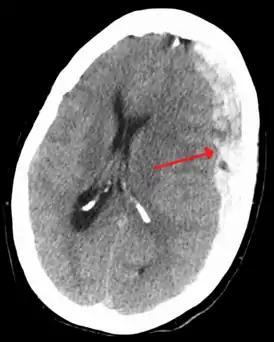

![]() Субдуральная гематома (обозначена стрелкой) со значительным смещением срединных структур. | |

При компьютерной томографии субдуральные гематомы имеют классическую серповидную форму, однако, могут выглядеть и линзовидно, особенно в начале кровотечения; это может вызвать затруднения в дифференциальной диагностике субдуральной и эпидуральной гематом. Более достоверным признаком субдуральной гематомы является её относительно большая распространённость по ходу полушария головного мозга с преодолением швов черепа, в отличие от эпидуральной гематомы. Субдуральная гематома также может выглядеть как «наслоение» повышенной плотности по ходу намёта мозжечка; такая гематома может быть хронической и стабильной, и косвенными минимальными признаками кровоизлияния могут служить сглаженность прилегающих борозд и медиальное смещение границы между серым и белым веществом.

Хронические гематомы при компьютерной томографии могут не дифференцироваться из-за своей изоденсивности мозговому веществу (иметь плотность вещества мозга), что затрудняет их выявление.